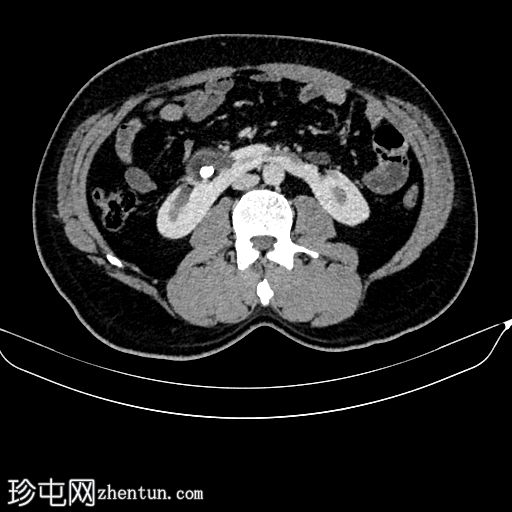

CT

轴位增强扫描(门静脉期)

双肾位置低于正常,位于肠系膜下动脉下方,位置更偏内侧,下极在腹主动脉前方中线处融合。

肾皮质厚度及强化均正常。

双侧肾盂朝向前方。

右侧肾盂轻度扩张,伴有结石。